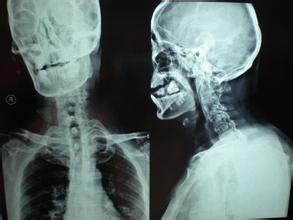

(1)致残率较高。由于强直性脊柱炎一般先侵犯骶髂关节,然后沿脊柱逐渐向上发展,而累及腰椎、胸椎、甚至颈椎受累脊柱不仅出现腰背疼痛,而且可同时出现进行性关节及脊柱活动功能受限,如病情进一步发展,则可使椎间盘、关节突及椎间各韧带都会发生骨化。在X线片上显示脊柱形成竹节状的骨性强直,有的则形成不同程度的驼背畸形,严重者不仅行动不便,而且两眼只能看地面的问号体形。